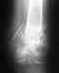

Вот снимок. Все врачи говорят, что операция обязательно. Но их мнения расходятся насчет выбора операции - одни советуют эту hook plate (да, судя по тому, что я видел в отделении травмотологии и изображениям этой пластины в интернете, это она), другие (НИИ ТО Новосибирска) говорят, что лучше лавсана еще ничего не придумано. С применением этих лавсановых нитей обещают 10-12 недель находиться в загипсованом состоянии. При этом аргументация против hook plate - стеснение движения, а также отсутствие эффекта восстановления связок. Я в растерянности, не знаю что делать. Учитывая цены, скорее всего останавлюсь на варианте без hook plate. Непонятно почему, тут либо вообще не делают операций с ними (то же НИИ ТО), либо делают с дорогими швейцарскими. Можете прокомментировать операцию с лавсановыми нитями (преимущества и недостатки относительно других методов) ? Как бы вы посоветовали поступить пациенту с таким диагнозом?